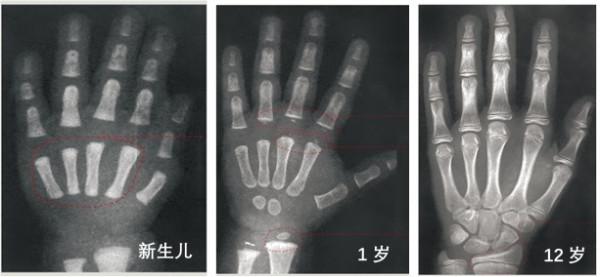

骨齡(bone age,BA)即骨骼年齡,是根據不同年齡各個骨化中心X線的特定影象出現時間不同來確定,其代表發育年齡,反映人體骨骼的成熟度。

一般是拍攝左手腕部加全手的X光片,觀察指骨、腕骨及橈、尺骨下端的骨化中心出現的時間、面積大小,判斷骨骼實際發育程度,來確定骨齡。